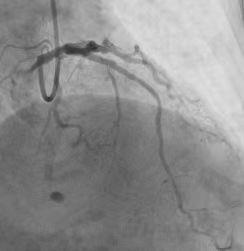

在市四医院心血管内科介入团队专家反复讨论和制定详细的预案之后,造影检查开始了。刘奶奶的病情比12年前明显加重,不但左侧血管堵塞达到95%,而且原本正常的右侧血管也已经完全堵塞。面对这种情况,只能分两次治疗。罗裕博士团队决定首先打通右侧血管。术中,钢丝顺利通过完全闭塞的位置,但是,由于刘奶奶血管钙化明显,球囊扩张始终不起作用,罗裕博士对病变立即进行了旋磨,每分钟16-20万转的磨头将血管内钙化斑块磨掉,最后,成功放入2枚支架。手术非常顺利,仅用了1个小时。

罗裕博士团队为刘奶奶修复后的右边血管

刘奶奶左边的血管比右边更加复杂,除了狭窄之外,还有分叉、钙化、血管瘤、扭曲,手术难度是平时的数倍。导丝艰难通过病变之后,交换旋磨导丝非常困难,在历经10多次旋磨之后,手术成功了。

罗裕博士团队为刘奶奶修复后的左边血管